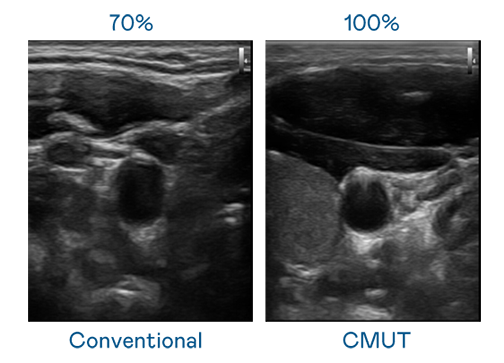

CMUT 技术是一种用电容式微机电元件来产生超音波讯号的技术。与传统 PZT 压电式技术相比,CMUT 频宽增加 30%,更宽频的超音波讯号让影像解析度大幅提升,是实现高影像品质医疗超音波扫描、促进精准医疗发展的关键技术。

大频宽带来超清晰影像

超音波影像的解析度高低,首先取决于探头能发出的讯号频宽。PT电子(中文)官网 CMUT 可提供高清晰的超音波讯号,提供高频宽、高灵敏度、影像纹理细节更高的超音波影像,协助医护人员缩短影像判读时间及利用精准的医疗影像进行诊断。